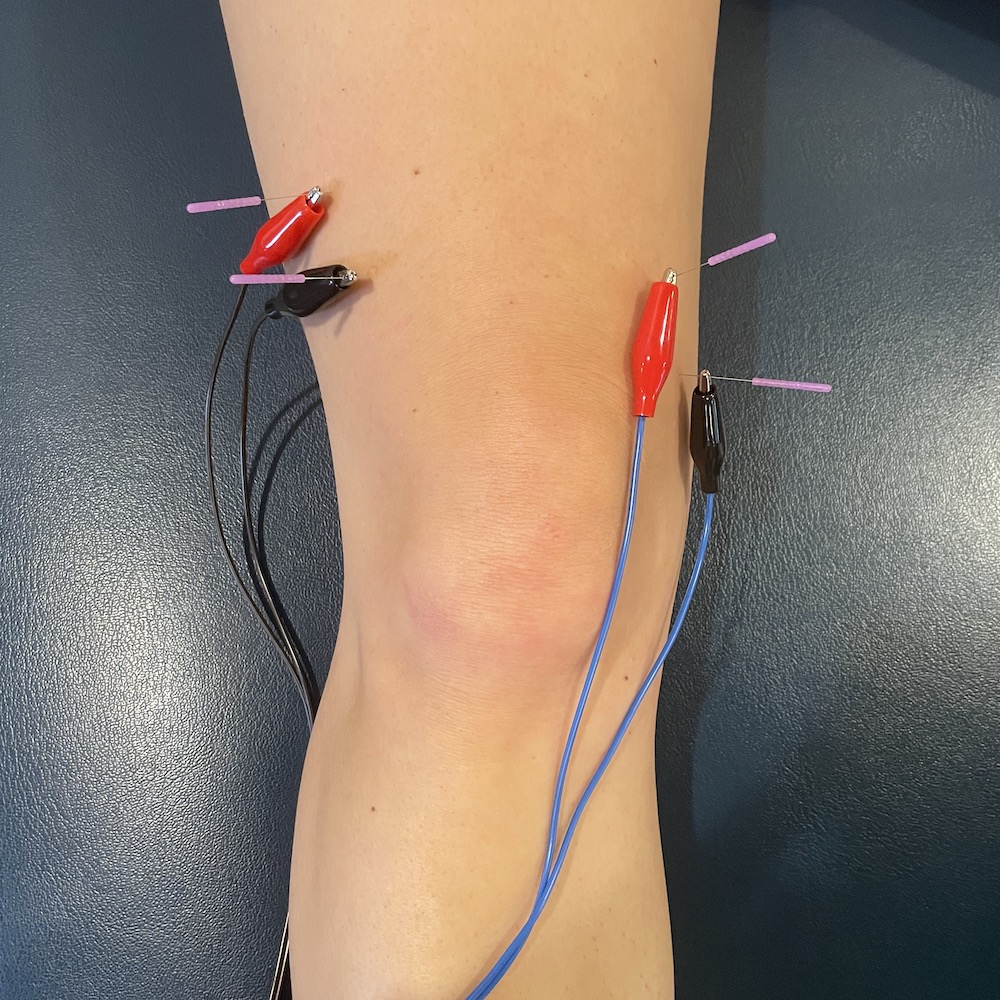

Elektro-Dry-Needling | Physiotherapie & Personal Training in Bonn

Dry Needling

Dry Needling for Manual Therapists points, Techniques and Treatments …

Physiotime – Dry Needling